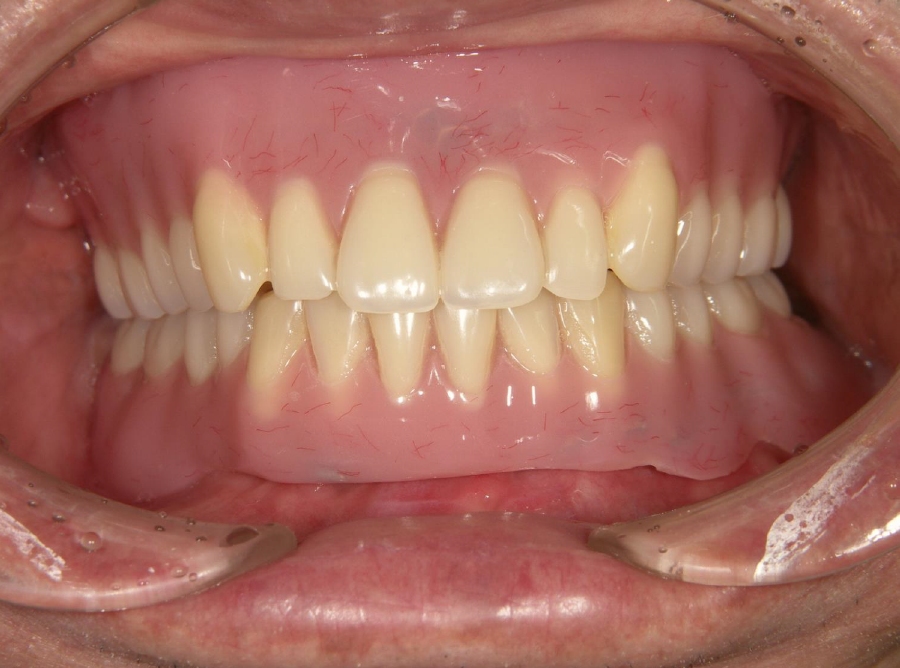

前歯インプラント症例

20代。交通事故で前歯を欠損。インプラント施術によって入れ歯から解放され前歯でしっかり食事できるようになりました。